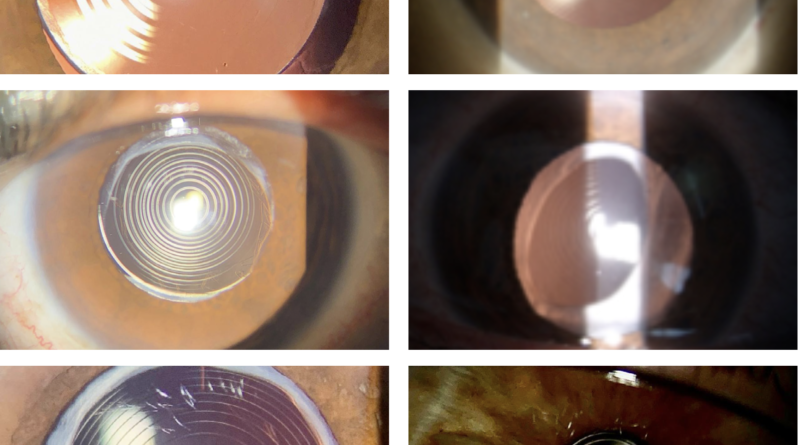

¿Qué es un lente intraocular?

Es un implante que utilizamos para reemplazar al cristalino (el lente que naturalmente tenemos dentro del ojo) cuando una persona es sometida a cirugía de catarata. Este lente tiene por objetivo permitir que la luz llegue de manera adecuada hasta la retina: la parte del ojo que capta la luz y permite que reconozcamos los objetos que vemos. Por tanto, tiene medidas acordes al tamaño del ojo y es personalizado.

Trifocales: una década de aprendizaje

Cada año, a medida que la población mundial envejece, el número de pacientes operados de catarata aumenta; sin embargo, el creciente número de personas que aún no han sido intervenidas es motivo de alarma. De acuerdo con la pirámide poblacional de 2022, la humanidad superó los 8 mil millones de habitantes, de los cuales 10.3 % tiene más de 65 años; es decir, en un futuro próximo más de 820 millones de personas probablemente requerirán cirugía de catarata